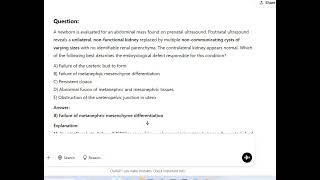

eQ-Exclusive MCQ Discussion Series on eMedicoz : Multicystic Dysplastic Kidney

DAMS eMedicoz : NEET PG, MBBS, FMGE, USMLE Prep

1K

3,807

5 лет назад